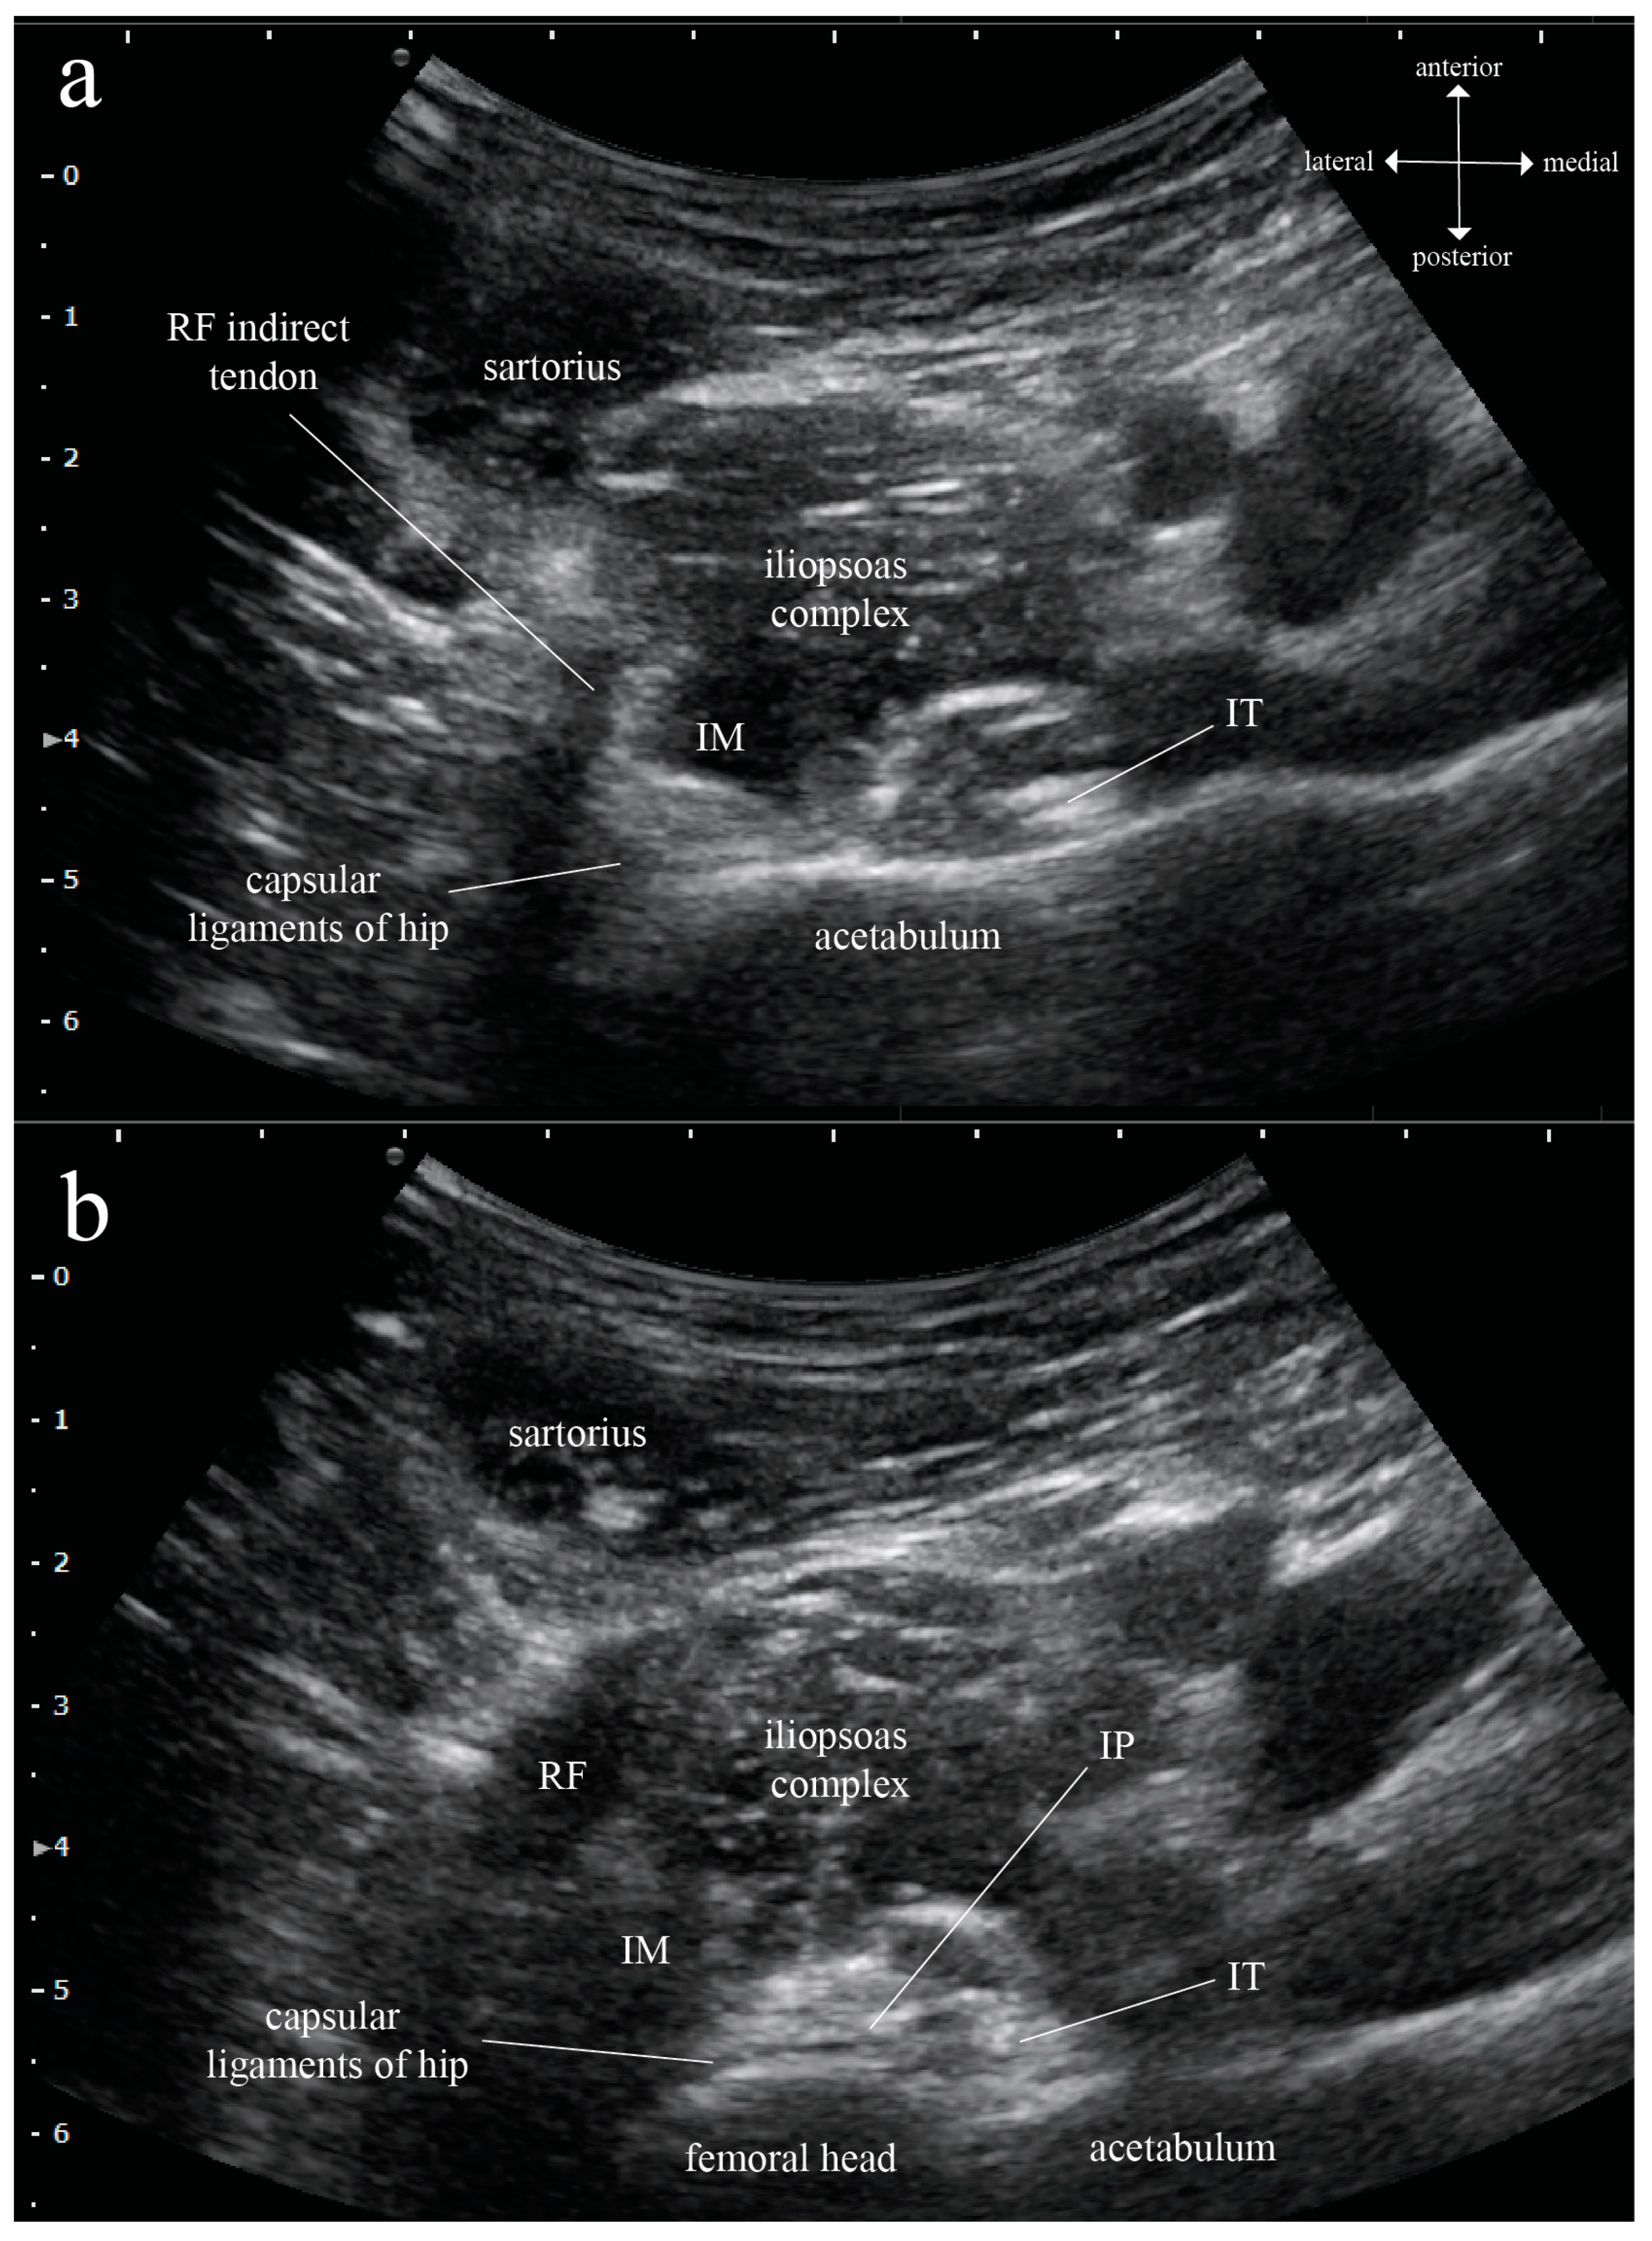

Parameters of Iliopsoas Plane Immediately Caudal to the Indirect Tendon of Rectus Femoris in Axial Plane Measured on Magnetic Resonance Images in an Adult Eastern Asian Population